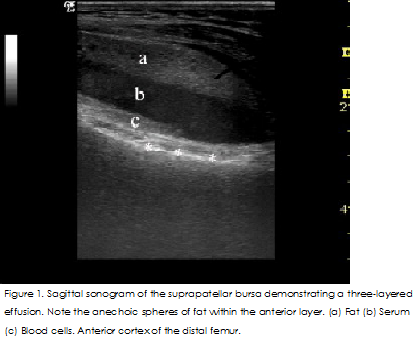

Cause Report